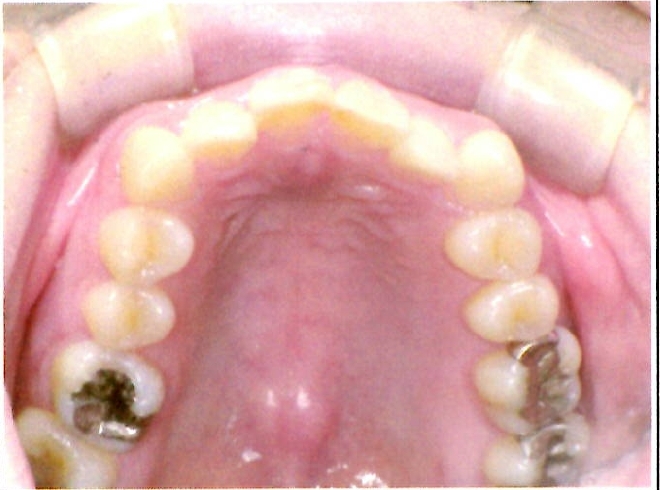

| 主訴・治療前の状態 | 著しい叢生(歯並びのガタガタ)があり、また6歳臼歯(第一大臼歯)が破折していた状態でした。 |

| 治療内容 | 通常の抜歯矯正では第一小臼歯(4番)を抜歯することが多く、その方が治療期間を短縮できますが、小川さんの場合は破折していた6歳臼歯を抜歯し、そのスペースを活用して歯列を整えました。これにより、健康な歯の本数を維持しながら矯正治療を行うことができました。 |

| 治療結果 | 治療前と比較して歯並びが大きく改善し、見た目も大幅に良くなりました。患者様にも大変喜んでいただけた症例です。 |